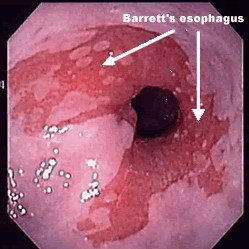

Barrett’s Esophagus

Squamous epithelium of the distal esophagus is replaced by intestinal-type columnar epithelium (aka Goblet cells) as a consequence of chronic reflux esophagitis.

Results in an increased risk of esophageal adenocarcinoma.

Barrett’s Esophagus - Gross Features

“Tongues of red” extending up